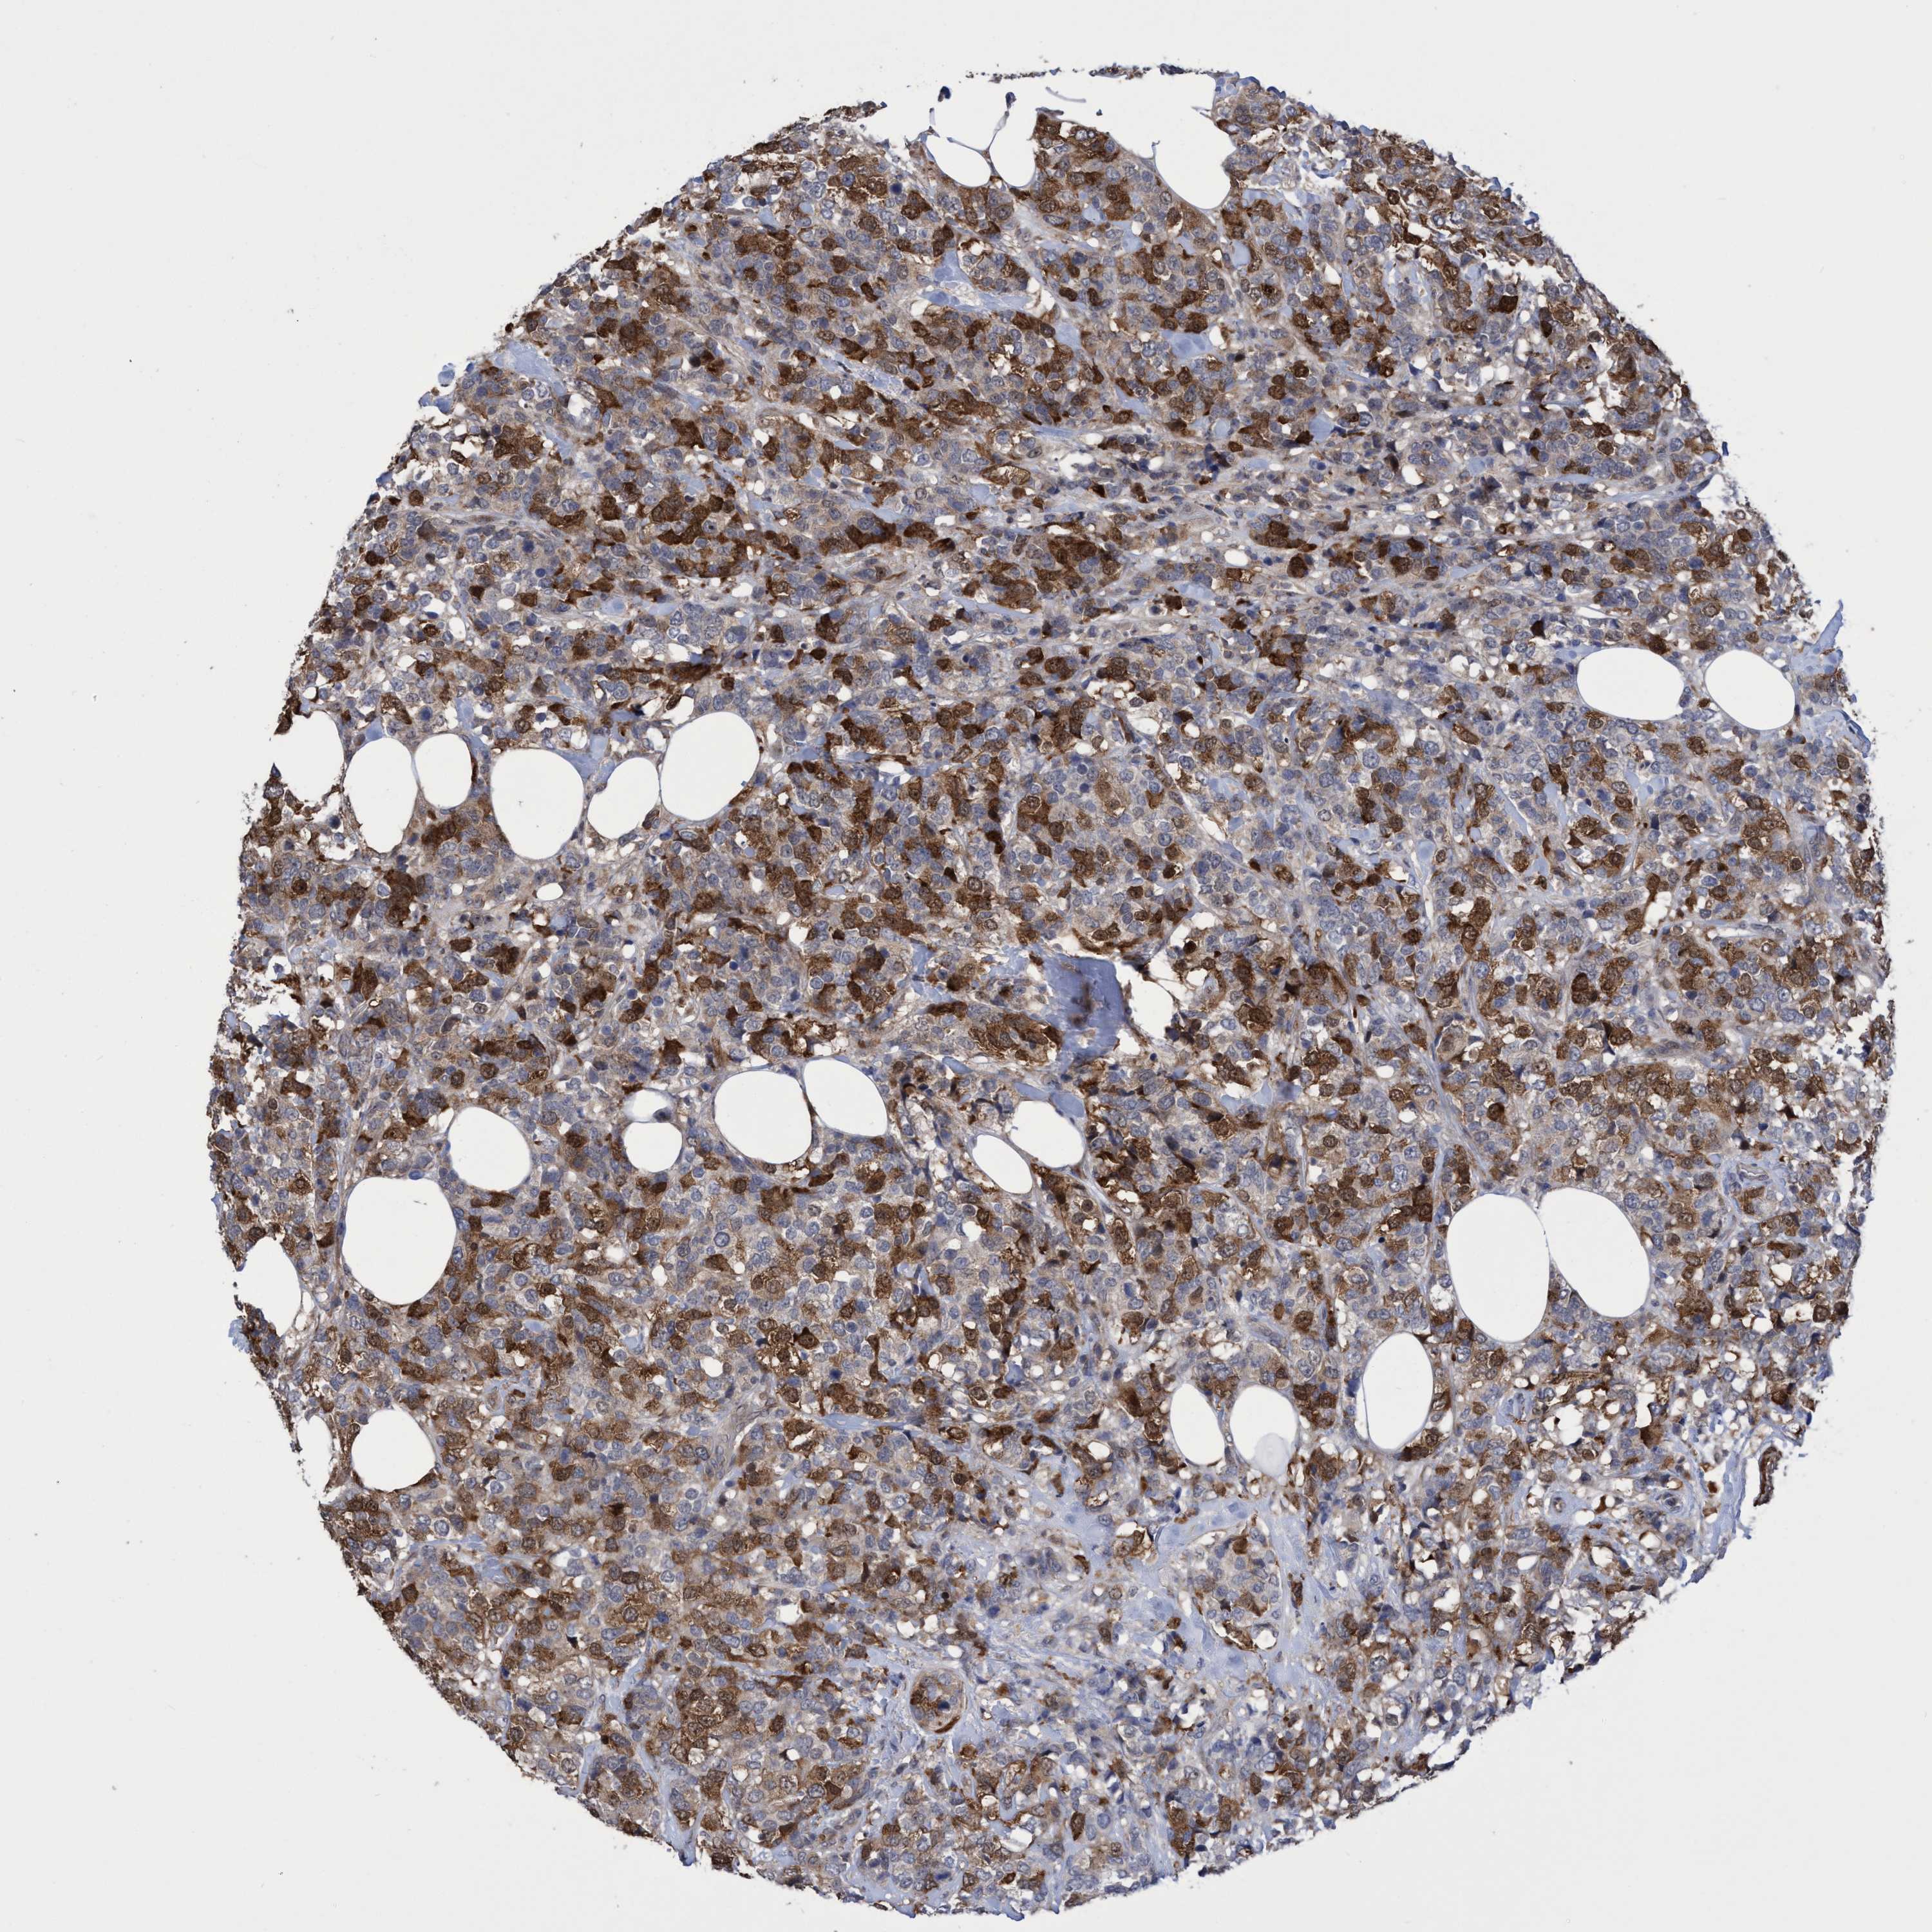

CANCER BREAST CANCER Show tissue menu

BRCA TCGA BRCA VALIDATION PROTEIN EXPRESSION